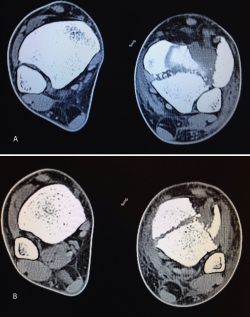

Figura 18. La tomografía computarizada muestra los fragmentos principales de la fractura, estando desplazado el Tillaux que se reduce con la tracción.

• Posibilidad de valorar y tratar lesiones asociadas (condrales y ligamentarias) (Figura 21).

Figura 21. Visualización directa del caso anterior.